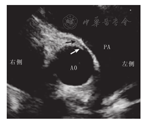

超声心动图是AAOCA优先选择的诊断方法,其优点在于便捷、经济、无风险,通常能观察到冠状动脉的起源及是否合并冠状动脉主动脉壁内走行,有经验的超声医师能快速准确地做出诊断。在健康小儿及青少年,超声心动图大动脉短轴切面可探查到左冠状动脉从左冠窦发出,右冠状动脉从右冠窦发出。而对于AAOCA的患儿,病变冠状动脉未从其正常的主动脉窦发出,多数患者可探及异常起源的冠状动脉开口。经胸超声心动图对于冠状动脉是否壁内走行多数可清晰显示(图3)。作者的经验认为,超声心动图对于是否合并壁内走行的判断优于心脏CT,是AAOCA是否合并壁内走行的最佳无创诊断手段。冠状动脉是否壁内走行对于指导外科医师手术决策具有重要意义。但需要注意的是,不少超声及临床医师对该病认识不足,有些运动性晕厥的AAOCA患者,在晕厥后不久就诊时心肌缺血较明显,左心室或右心室心肌会出现缺血水肿,在超声心动图上会有心肌稍增厚及收缩功能减低,加之该病心肌酶及肌钙蛋白增高,如不注意,会误诊为暴发性心肌炎。另外在临床工作中,对于儿童及青少年超声检查,超声医师往往侧重于心脏及大血管有无异常分流、心脏有无扩大及心脏瓣膜有无病变等情况,而忽视对冠状动脉的仔细探查,这也是造成漏诊的原因之一[14]。如果应用当前主流的心脏超声仪器仔细对冠状动脉进行探查,冠状动脉起源、是否壁内走行及冠状动脉开口有无狭窄等情况多数能清晰显示。

注:AO:主动脉;PA:肺动脉;黑色箭头所示为右冠状动脉,白色箭头所示为右冠状动脉壁内走行段;该例壁内走行段较短,冠状动脉开口无明显狭窄 AO:aorta;PA:pulmonary artery.The right coronary artery was marked as the black arrow while the intramural part was indicated as the white arrow.In this case,the ostium of right coronary artery is not narrow for its short distance of intramural course